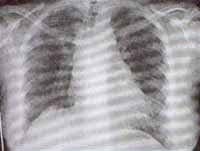

Se toma una Radiografía de tórax (Figura 1) que muestra infiltrados intersticiales difusos con componente micronodular, con disminución global del volumen de los pulmones. La paciente fue sometida a fibrobroncoscopia con biopsia transbronquial, la cual es informada como enfermedad granulomatosa crónica compatible con TBC.

Figura No 1. Radiografía del tórax inicial